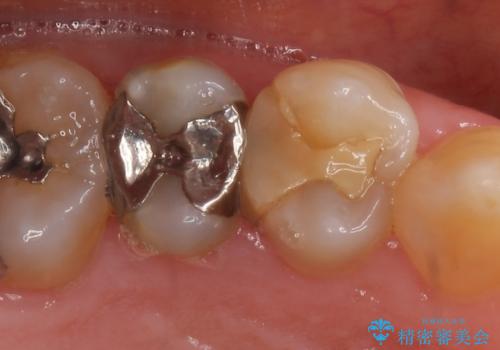

PGA(ゴールド)インレー 深い虫歯の虫歯の治療